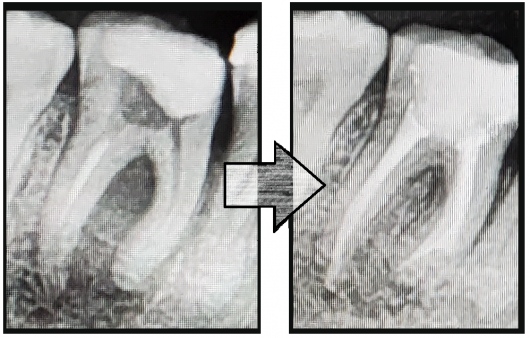

Jestem Amerykaninem, ale mieszkam w Polsce ponad 10 lat. Zajmuję się zachowawczą, leczeniem kanałowym pierwotnym i wtórnym pod mikroskopem, protetyką i prostą chirurgią. Wykonuję też Bonding i Flow Injection Technique.

Endodoncja mikroskopowa

Leczenie endodontyczne